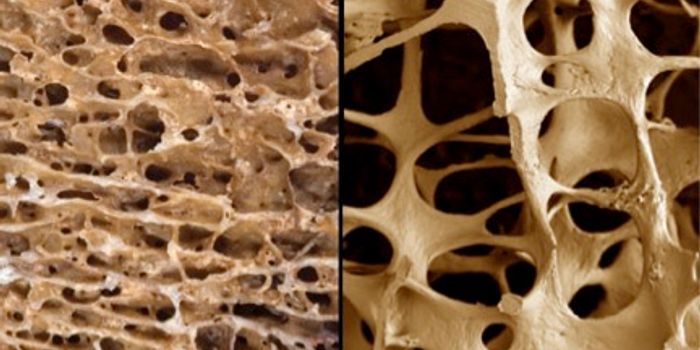

APR 05, 2016Clinical & Molecular DXA recent study found that treating osteoporosis brought on by hyperparathyroidism with conventional drugs could actually ...